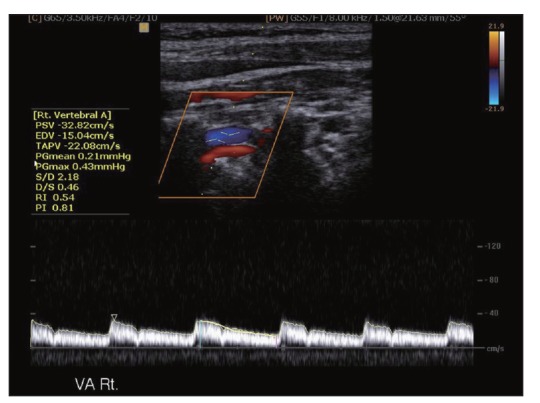

Funkcionális vizsgálat

A képen az artéria vertebralis vizsgálatát láthatjuk, ami a nyaki verőerek egyike. Color doppler vizsgálat során az áramlásról színkódolva kapunk információt. Alatta az úgynevezett áramlási görbét láthatjuk. Ilyen vizsgálat során az áramlási sebességek számszerű mérésére is van lehetőség.

Az érnek csak kis szakaszát láthatjuk, és mellettük sötét megjelenésű területek vannak. Ez azért van mert, ezek az erek a csigolyák harántnyúlványai által képzett csontos csatornában futnak. A csatorna nem teljesen zárt, így az ér a két csigolya közötti térben vizsgálható. Jó példa ez a kép arra is, hogy a csontos struktúrák hogyan takarják ki a mögöttük lévő képleteket.